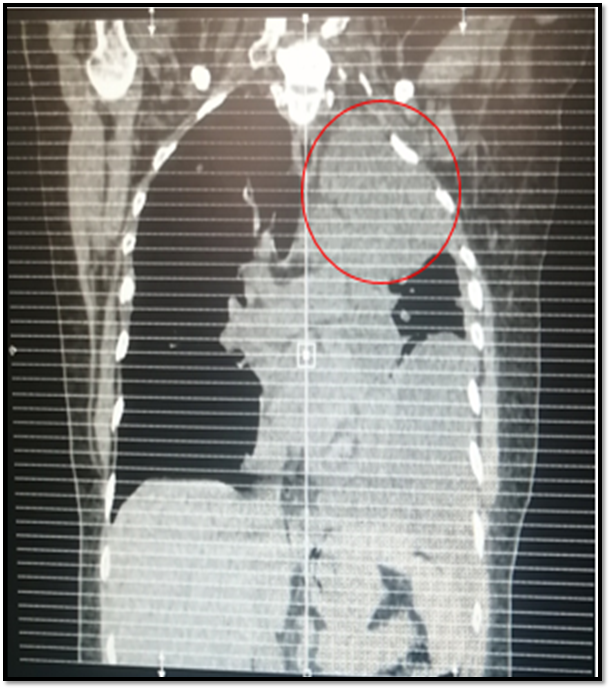

The next study to be requested will be the computerized axial tomography of the simple thorax, which will describe in a more specific way the size, location and extension of the lesion, as well as the presence of lesions suggestive of metastasis at lymphatic and bone level. Another alternative study is MRI of the chest, with similar sensitivity and specificity.

From the outset, a chest radiography is requested, where there is evidence of left pleural effusion that takes the base and third, where the opacity of approximately 5x5cm in the upper ipsilateral vertex draws attention. A sample of this pleural fluid (cytological, cytochemical and culture) is taken, this being negative. Simple chest tomography is performed where the following is observed:

@anaestrada12

Space-occupying lesion with mass effect at left pulmonary vertex level of approximately 5x 7,2cm. Accompanied by septate ipsilateral effusion.

Suggestive images of bone metastasis at t5, t4 and sternum levels are also observed.